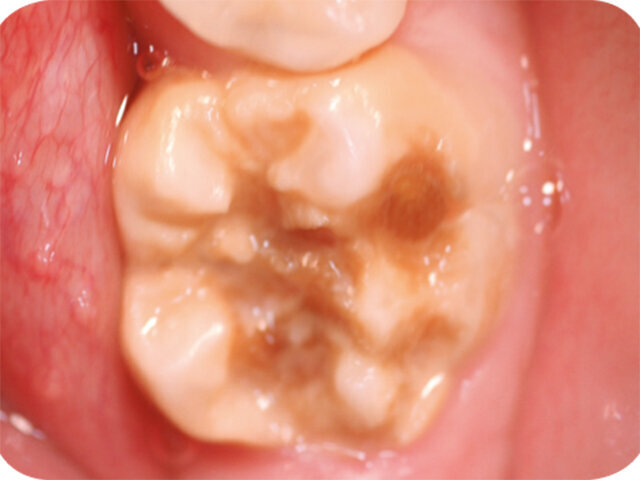

Molárová a incizální hypomineralizace skloviny (Molar Incisor Hypomineralisation – MIH) je globální problém postihující každé sedmé dítě. MIH je běžná vývojová porucha postihující především jeden nebo více prvních stálých molárů. Centrální řezáky mohou být rovněž postiženy, většinou však v menší míře. Může též dojít k hypomineralizaci druhých dočasných molárů (Hypomineralised Lesions on Second Primary Molars – HSPM, hypomineralizační léze druhých stálých molárů) nebo špičáků. U dětí s HSPM je až pětkrát vyšší pravděpodobnost vzniku MIH u stálého chrupu. Závažnost se velmi liší od mírných opacit k posterupčnímu odlomení skloviny.

Klinický vzhled

- Ohraničené opacity v rozpětí od krémově bílé, přes žlutou až po hnědé diskolorace

- Poškozená sklovina má normální tloušťku (dokud nedojde k posterupčnímu odlomení skloviny)

- Rychlá progrese zubního kazu

- Posterupční odlomení skloviny